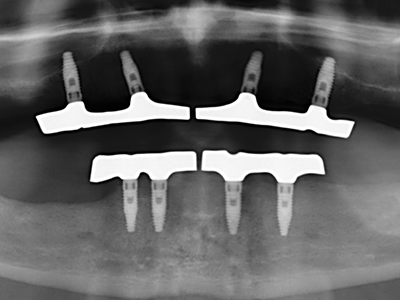

Como ya se ha demostrado en el pasado, básicamente cualquier procedimiento de cirugía de hueso representa una posible indicación para la cirugía piezoeléctrica. Así, la preparación del segmento móvil en la osteogénesis de distracción (fig. 23-25) y en la osteotomía de sándwich puede realizarse con piezas especiales, sin poner en peligro el suministro sanguíneo de la parte crestal, que resulta esencial para el éxito de ambas técnicas (González-García, Diniz-Freitas et al. 2008).

Para la extracción de implantes es posible realizar la preparación de una tapa ósea vestibular que, tras retirar el tornillo del implante, vuelve a fijarse y, de este modo, mantiene el contorno de la apófisis alveolar.